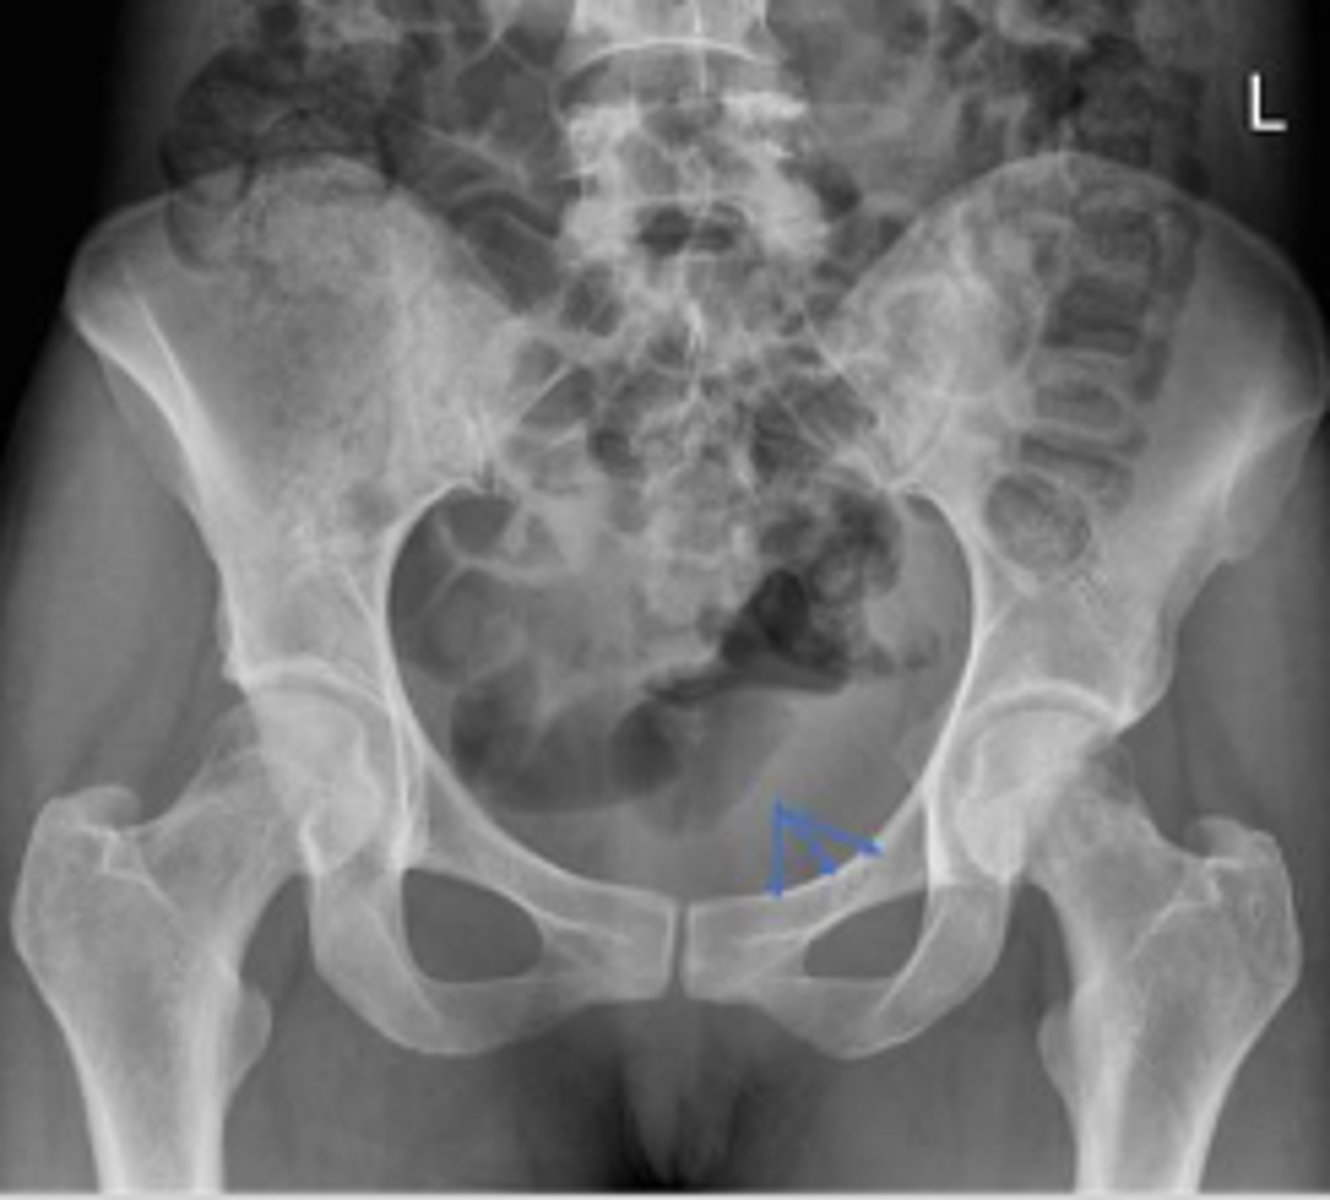

Bilateral frog leg view

What is the name of the radiographic view?

Phleboliths

What are the arrows pointing to?